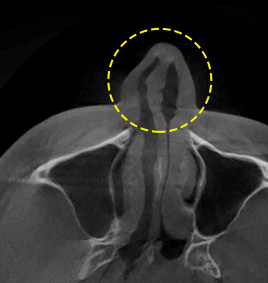

ศัลยกรรมจมูก 3D-CT ไม่เพียงแต่จำแนกองค์ประกอบด้านนอกของจมูกเท่านั้น แต่ยังรวมทั้งอาการและสาเหตุที่ก่อปัญหาต่อกระดูกในโพรงจมูก จมูกคด กระดูกกั้นผนังโพรงจมูก อาการคัดจมูก ฯลฯ อีกด้วย การวิเคราะห์ 3 มิติที่ใช้เทคโนโลยี 3D-CT ช่วยเตรียมแผนการทำศัลยกรรมที่เหมาะสม ลดปัญหาต่อเส้นเลือดและเส้นประสาท แถมยังเป็นขั้นตอนศัลยกรรมที่ปลอดภัยและแม่นยำอีกด้วย

เฟซใช้อุปกรณ์ 3D-CT ที่ทันสมัยเพื่อวิเคราะห์ลักษณะโดยรวมของกระดูกโพรงจมูก กระดูกอ่อนผนังกั้นโพรงจมูก เนื้อเยื่อผิวหนัง ความอสมมาตร ฯลฯ ซึ่งไม่สามารถจำแนกออกมาโดยใช้วิธีการให้คำปรึกษาปกติทั่วไป เพื่อช่วยให้ขั้นตอนศัลยกรรมจมูกปลอดภัยและแม่นยำมากขึ้น